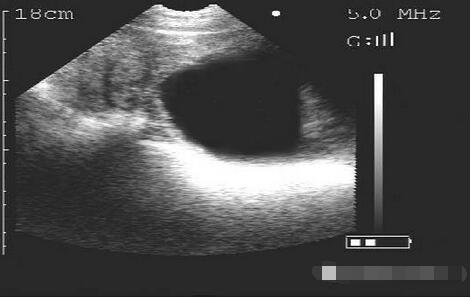

未怀孕检测图(1/7)